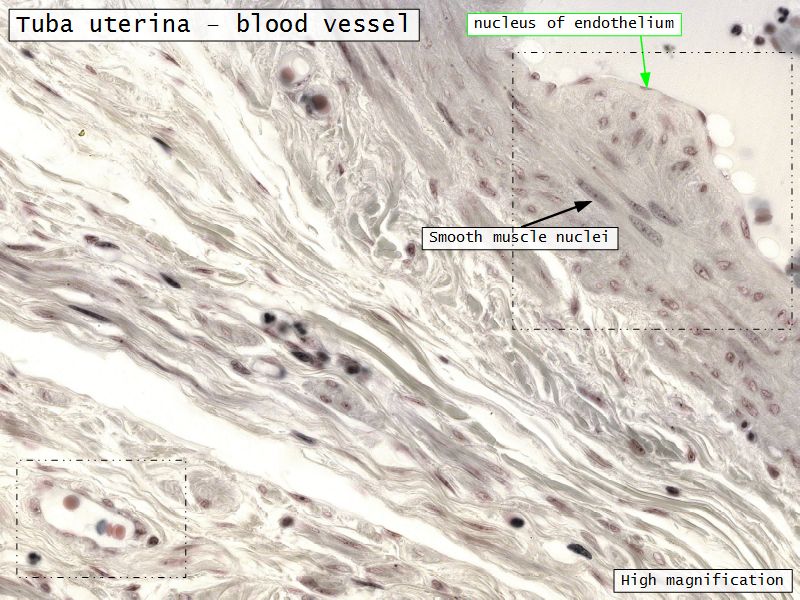

Tuba uterina

Tuba uterina

- Muscular tube

- Most frequent site of fertilization

- Conveys zygote to uterus

- Four regions

- Three layers

Three layers

- Mucosa

- Muscular layer

- Serosa

Muscular layer

- Ill-defined

- Inner circular

- Outer longitudinal

- Play role in moving zygote towards uterus

Serosa

- Simple squamous epithelium

- Contains

- Blood vessels

- Lymphatics

- Nerves